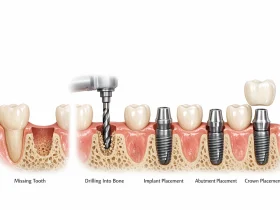

برای درک بهتر علائم خرابی ایمپلنت، ابتدا باید بدانیم ایمپلنت چگونه در دهان قرار میگیرد و چه عواملی باعث موفقیت آن میشوند. ایمپلنت در واقع پایهای فلزی است که درون استخوان فک قرار میگیرد و پس از مدتی با استخوان جوش میخورد. این فرآیند که «اُسیواینتگریشن» نام دارد، مهمترین مرحله در موفقیت ایمپلنت است.

اگر این اتصال بین استخوان و ایمپلنت به درستی شکل نگیرد، احتمال شکست درمان افزایش مییابد. گاهی نیز ایمپلنت در ابتدا کاملاً موفق است اما به مرور زمان و به دلیل عفونت، فشار زیاد یا تحلیل استخوان دچار مشکل میشود.

به طور کلی شکست ایمپلنت میتواند در دو مرحله اتفاق بیفتد. مرحله اول شکست زودهنگام است که معمولاً در ماههای ابتدایی پس از جراحی رخ میدهد و بیشتر به مشکلات جوش خوردن ایمپلنت با استخوان مربوط میشود. مرحله دوم شکست دیرهنگام است که ممکن است چند سال پس از کاشت ایمپلنت اتفاق بیفتد و معمولاً ناشی از عفونت، تحلیل استخوان یا فشارهای مکانیکی است.